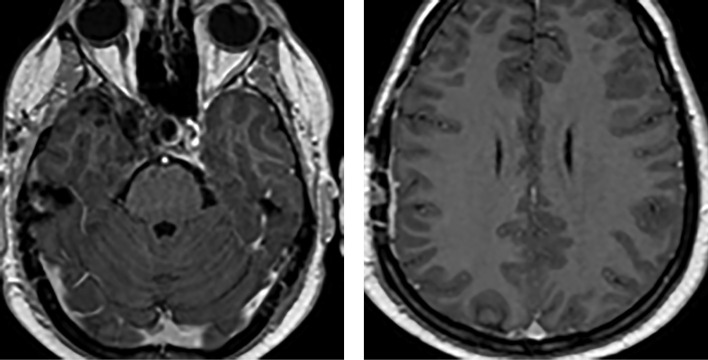

垂体癌(垂体转移性神经内分泌肿瘤)是指已证实有颅脑和/或全身转移的垂体肿瘤。这类肿瘤极为罕见,仅占所有垂体瘤的 0.1%至 0.5%,死亡率很高。在本病例中,一名年轻患者在出现侵袭性复发性分泌催乳素垂体瘤 25 年后被诊断为垂体癌伴颅内转移。标准治疗(转移灶切除、放射治疗、卡麦角林治疗)使病情长期缓解。

Pituitary carcinoma (metastatic neuroendocrine tumor of the pituitary gland) is the pituitary tumor with confirmed craniospinal and/or systemic metastases. These tumors are extremely rare accounting for only 0.1% to 0.5% of all pituitary tumours and are characterized by high mortality. In the presented case, pituitary carcinoma with intracranial metastasis was diagnosed in a young patient 25 years after manifestation of an aggressive recurrent prolactin-secreting pituitary tumor. Standard therapy (removal of metastasis, radiation therapy, cabergoline therapy) resulted in a long-term remission of the disease.